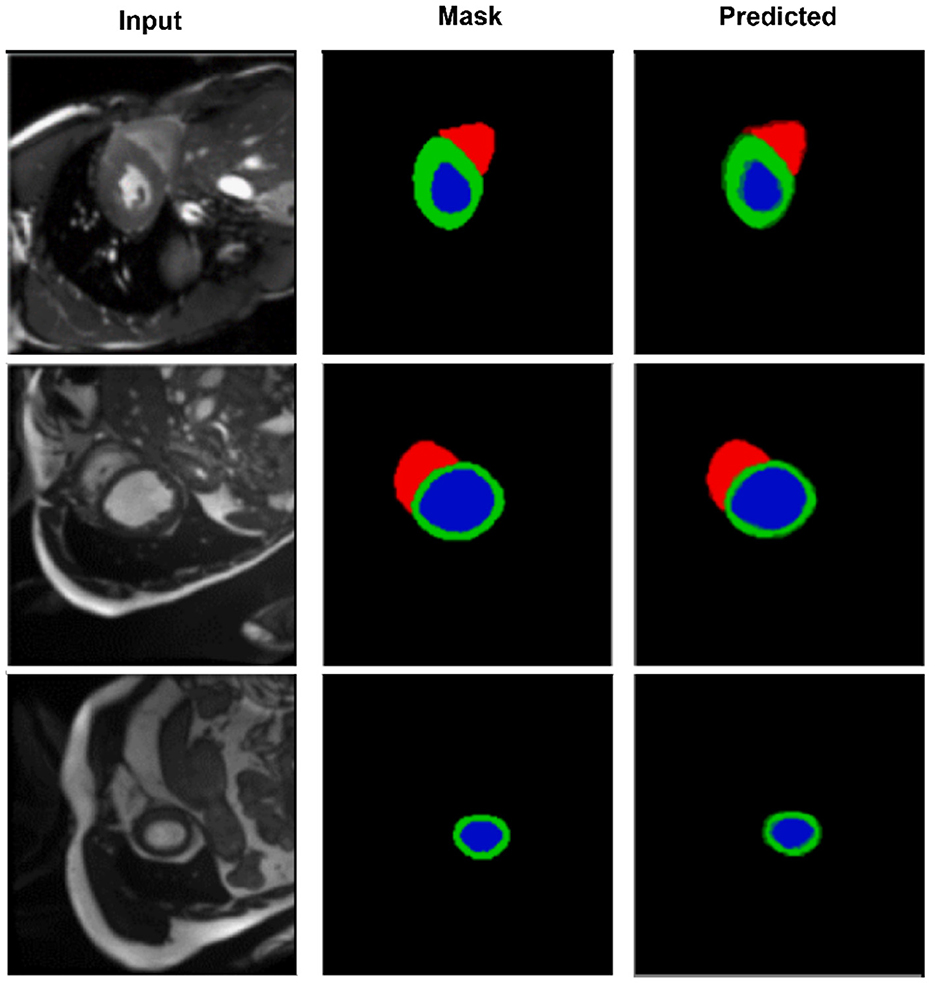

Accurate segmentation of cardiac structures in magnetic resonance imaging (MRI) is essential for reliable diagnosis and quantitative analysis of cardiovascular diseases. However, conventional convolutional neural networks often struggle to maintain both semantic consistency and geometric smoothness, particularly in challenging slices with high anatomical variability. In this work, we propose CASNet, a novel U-Net-based architecture that integrates three key enhancements to address these limitations. First, we introduce a Multi-Scale Context Block (MSCB) at the network bottleneck to enrich encoder features with diverse receptive fields, enabling robust representation of cardiac structures across varying spatial scales. Second, we replace standard skip connections with Cross-Attentive Skip Connections (CASC), allowing the decoder to selectively aggregate spatial features from encoder layers via attention-weighted fusion. This mitigates semantic mismatch and promotes more effective feature reuse. Third, we incorporate a Curvature-Aware Loss that penalizes second-order spatial discontinuities in the predicted segmentation, thereby improving the smoothness and anatomical plausibility of the boundaries. Extensive experiments on the ACDC dataset demonstrate that CASNet outperforms baseline U-Net models and recent attention-based architectures, achieving superior performance in both region overlap and boundary accuracy metrics. The proposed approach provides a robust and generalizable solution for high-precision cardiac MRI segmentation, which may serve as a foundation for future downstream clinical applications in AI-assisted cardiac analysis.